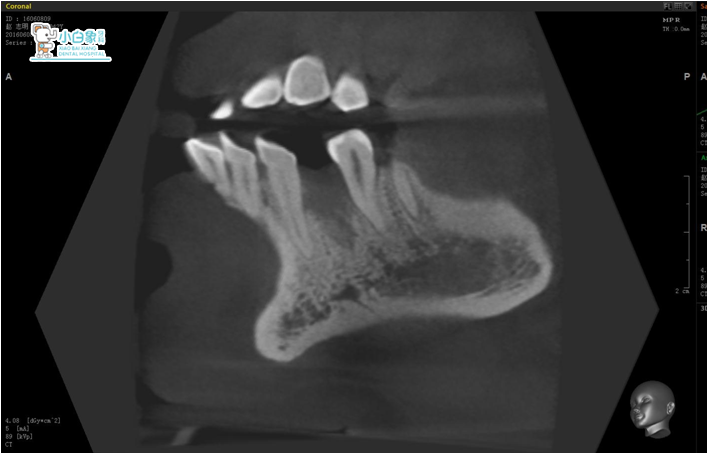

图片3备洞

备洞

2016年8月25日   34消毒,拆线2017年1月13日     二期